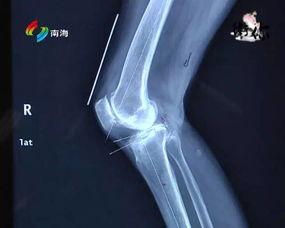

接下来,手术过程正式开始。医生首先会对患者的膝关节进行清理,去除受损的关节面。将人工膝关节植入,并进行调整。这一过程需要医生具备高超的技艺和丰富的经验。在视频里,你可以清晰地看到医生如何精准地操作,让患者重获健康。